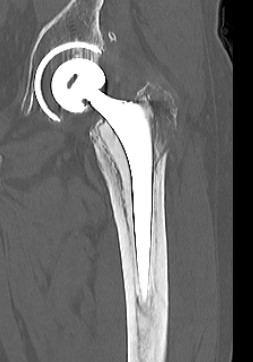

Fracture with stem subsidence around a polished tapered femoral stem treated with ORIF